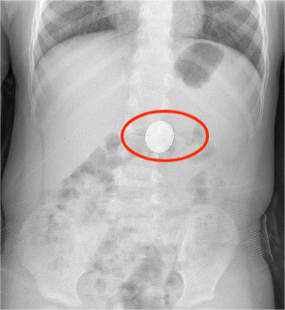

孩子误吞离子电池怎么办?

如果孩子误吞了离子电池,首先要立即联系医生或医院急诊室,并尽快采取行动。离子电池可能会对孩子造成严重的伤害,甚至危及生命。因此,要立即采取措施,确保孩子的安全。

无锡:男孩误吞纽扣电池,在死神手里挣扎了一年多, 你怎么看?

昨天看了这个消息,底下有个儿科医生说,这个宝宝的情况适合做食管切除手术,把烧坏了,软化了的地方切掉,再怎么接上。说南京儿童医院知道哪个医院做这种手术成功率高,可以让孩子父母咨询一下。